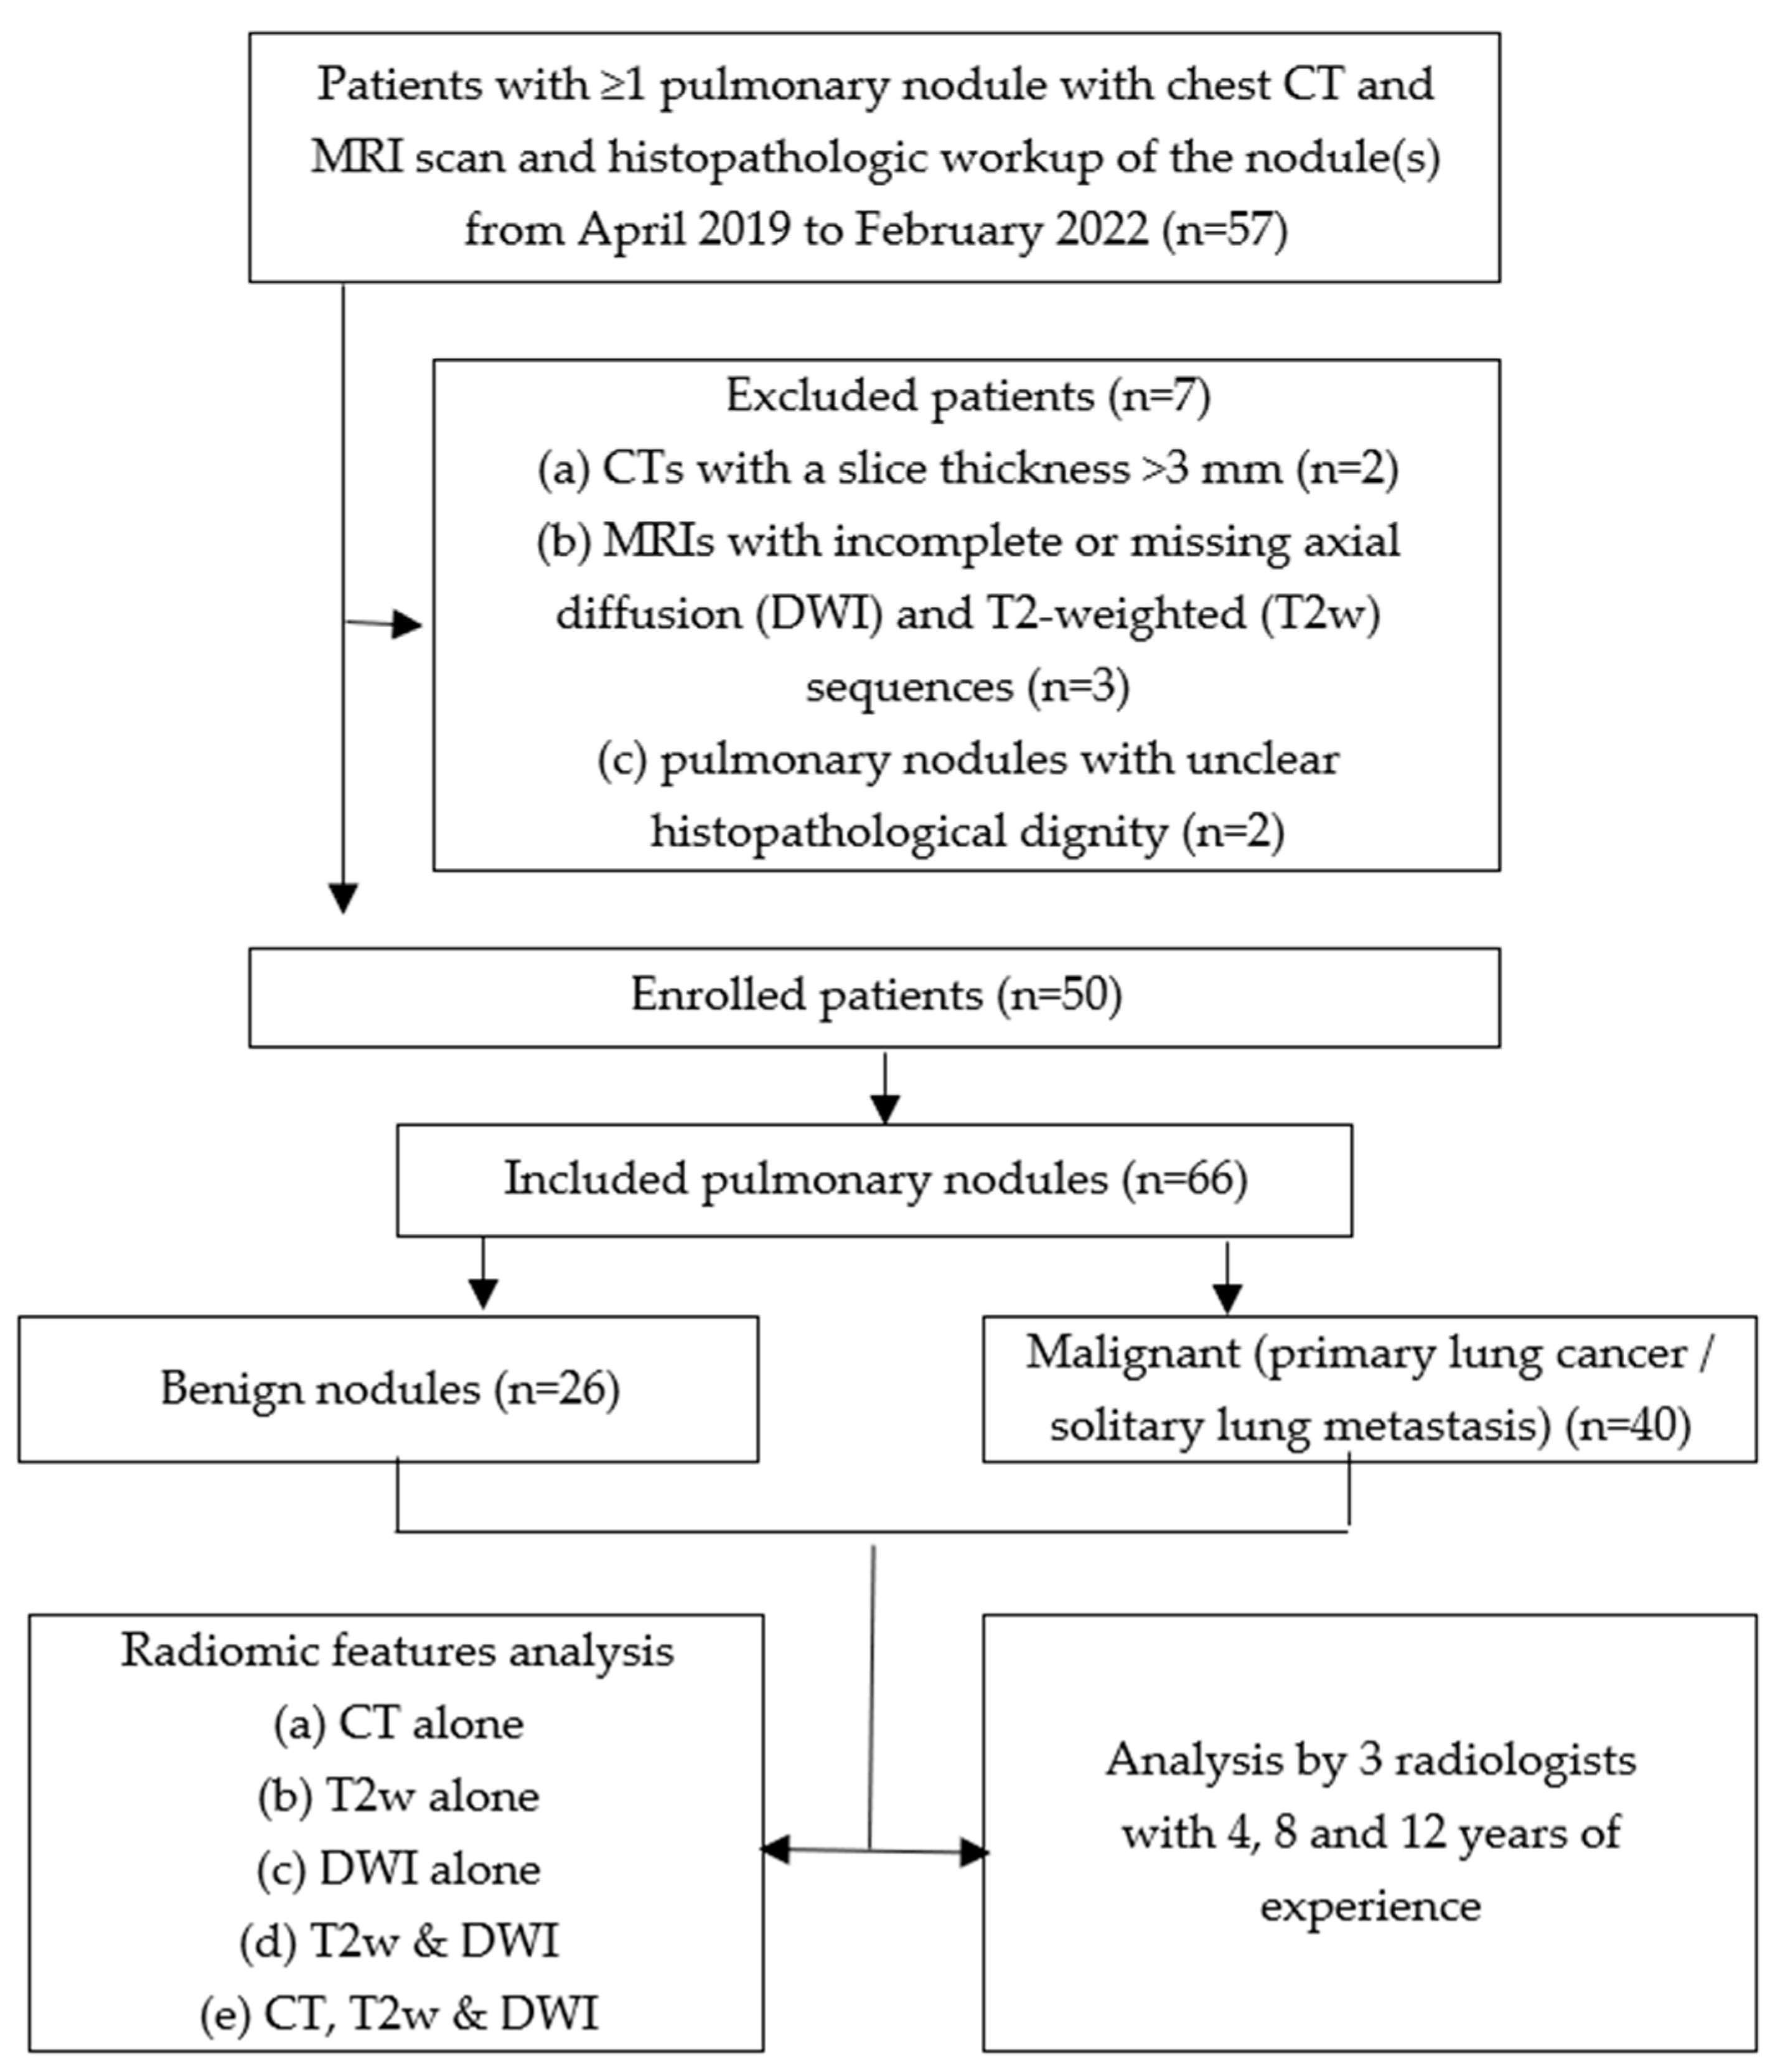

2.1. Study Design and Sample